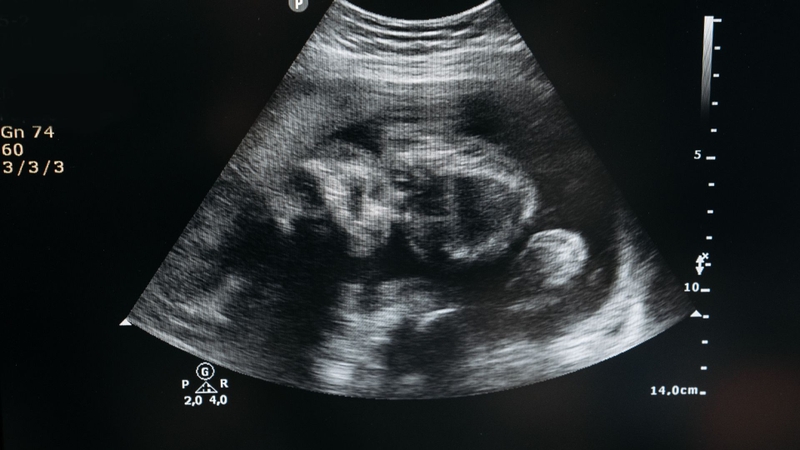

Siêu âm ở tuần 18 là một bước kiểm tra quan trọng để đánh giá sự phát triển của thai nhi và phát hiện sớm các bất thường nếu có. Đây cũng là dịp để mẹ nhìn thấy bé yêu rõ hơn qua màn hình siêu âm. Đồng thời, bác sĩ có thể kiểm tra một số thông tin cơ bản sau:

Mặt khác, chuyên gia sẽ đánh giá những chỉ số siêu âm quan trọng phản ánh sự phát triển khỏe mạnh của bé, bao gồm:

Những chỉ số này giúp bác sĩ đánh giá xem thai nhi có phát triển đúng chuẩn hay không. Nếu có bất kỳ dấu hiệu bất thường nào, bác sĩ sẽ tư vấn thêm để mẹ có hướng xử lý kịp thời.